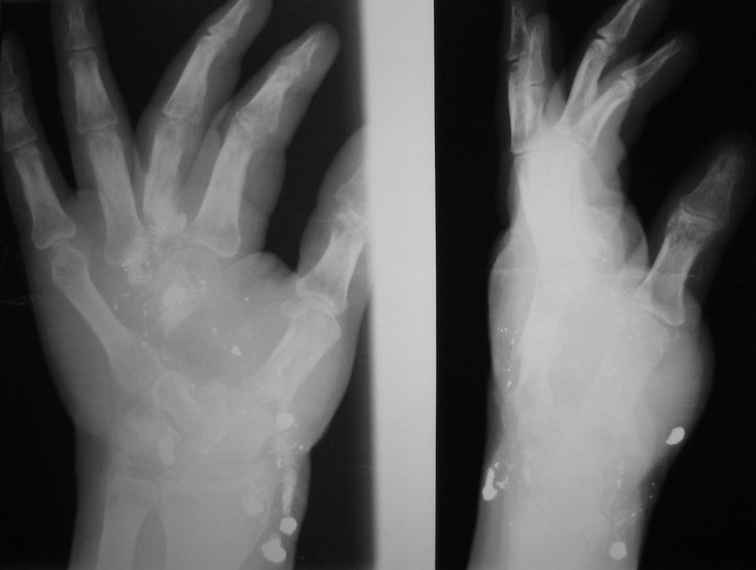

Больной 30 лет получил проникающее огнестрельное дробовое ранение с повреждением правого легкого, печени и правой кисти в октябре 2006г. С проблемами в легком и печени справились,теперь необходима реконструктивная операция на правой конечности.

На рентгенограммах правой кисти в 2-х проекциях регионарный остеопороз. II, III, IV пястные кости отсутствуют. Дефект в проксимальной трети I пястной кости.

Сросшиеся переломы основных фаланг III и IV пальцев правой кисти.

В проекции мягких тканей множественные металлические инородные тела.

Повреждены и сухожилия сгибателей, движений в II, III, IV пальцах нет, хотя чувствительность сохранена.